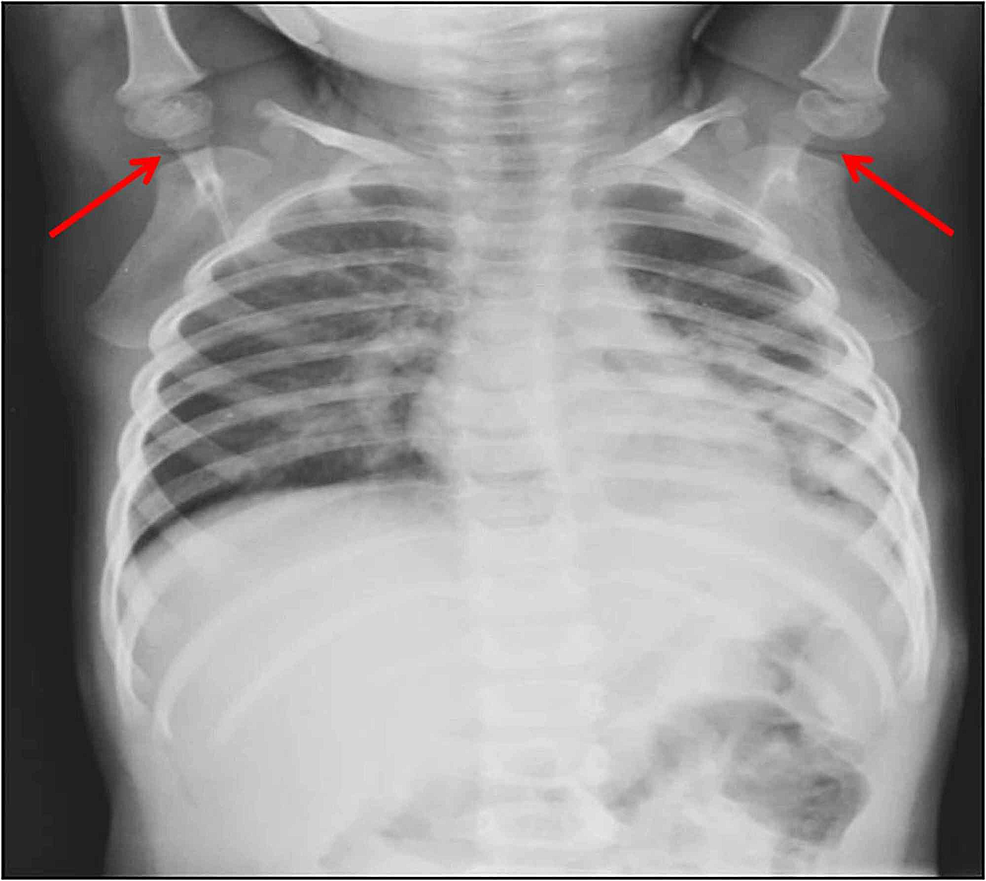

Vacuum phenomenon in the shoulder of a child BMJ Case Reports What Is Vacuum Joint Phenomenon The vacuum phenomenon (vp) is an anatomical entity that has the potential to cause confusion in the diagnosis and evaluation of joint pathologies. Intervertebral vp is usually associated with. ‘vacuum phenomenon’ or ‘pneumoarthrosis’ term is used when there is air within a joint space. ‘vacuum phenomenon’ or ‘pneumoarthrosis’ term is used when there is air within a joint space. It. What Is Vacuum Joint Phenomenon.

Vacuum phenomenon in the shoulder of a child BMJ Case Reports What Is Vacuum Joint Phenomenon ‘vacuum phenomenon’ or ‘pneumoarthrosis’ term is used when there is air within a joint space. It is a very common occurrence, particularly in external rotation. It has been described commonly in the spine and. The vacuum phenomenon (vp) refers to collection of gas within the joint space. The vacuum phenomenon (vp) is an anatomical entity that has the potential to. What Is Vacuum Joint Phenomenon.